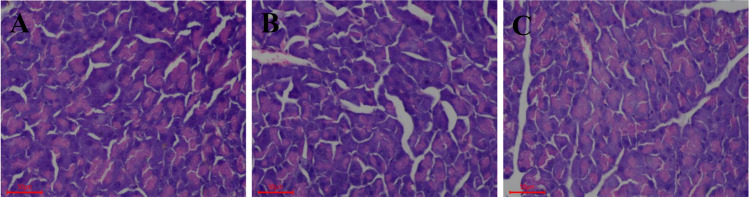

Effect of L. plantarum Y15 administration on prevention of pancreas injury

Histopathological examination of the pancreas is shown in Fig. 2. The structure of pancreatic islet cells was normal, cells were arranged closely and have clear cellular characteristic, and no obvious pathological damage was observed in the NC group. However, some pathological changes in islets of the MC group, such as irregular structure, reduced volume of islet cells, and ballooning degeneration. L. plantarum Y15 administration improved cell damage to some degree by increasing the number of islets and decreasing β-cell necrosis and vacuolization.

Fig. 2.

Effect of L. plantarum Y15 administration on pancreas histopathological alterations. (A) NC group; (B) MC group; and (C) Y15 group